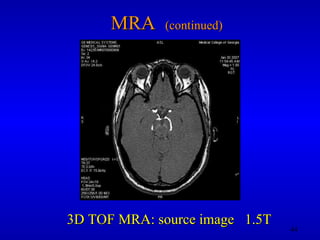

MRA  (continued) 3D TOF MRA: source image  1.5T

MRA (continued)3D TOF MRA: source image 1.5T